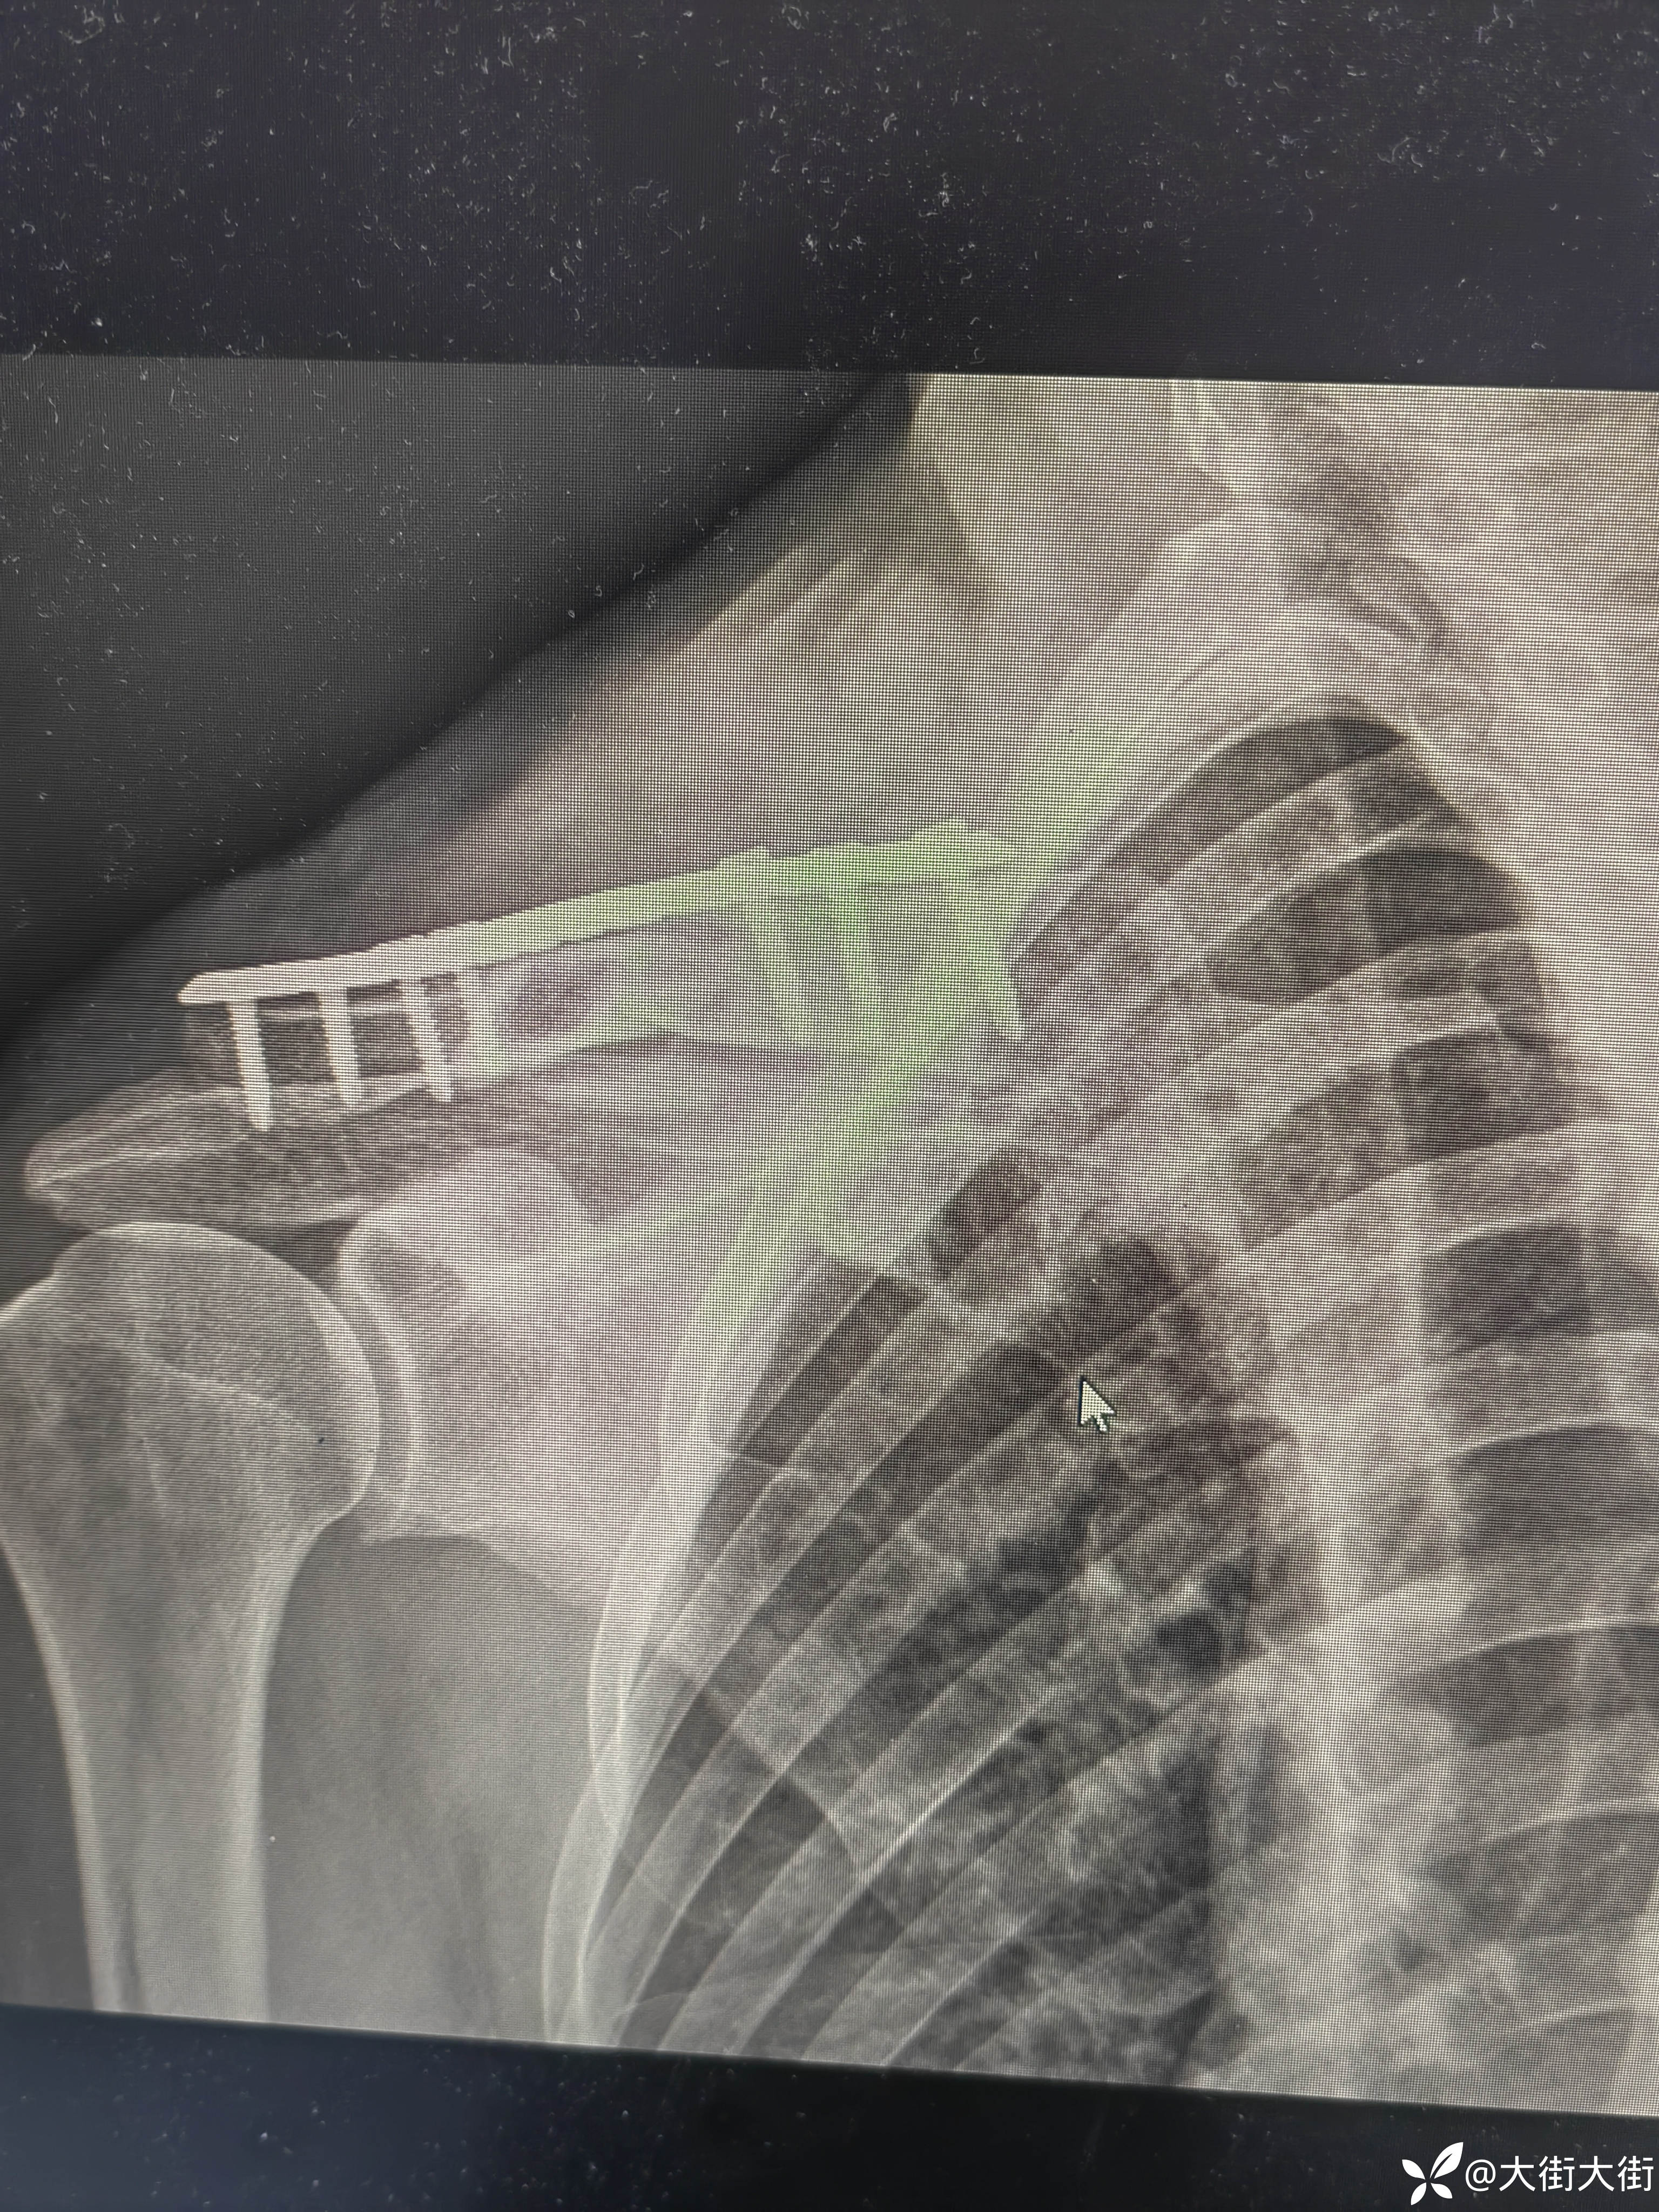

第一次做锁骨mipo,请各位老师指导。

【患者信息】:男,61岁

【主诉】:外伤致右肩部疼痛,活动受限3天。

第一次做,比想象中要难点,第一感觉就是明显的视野受限。板子放的不是很完美,切口位置没把握好,下次用马克笔画一下。各位老师轻点喷。